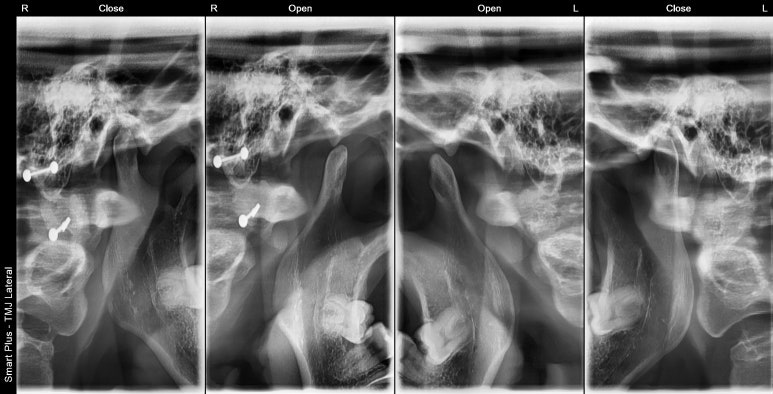

우선 치과에 내원하시면 파노라마 엑스레이와 3D CT 촬영을 통해 전체적인 뼈와 턱관절의 구조를 확인하고 문제가 없는지 살펴봅니다.

턱관절 질환 여부 확인이 가능한 파노라마 엑스레이와 CT 촬영 기기

턱에서딱딱소리가 나는 경우 촬영해 턱관절과 디스크의 이상 여부를 확인하는 엑스레이